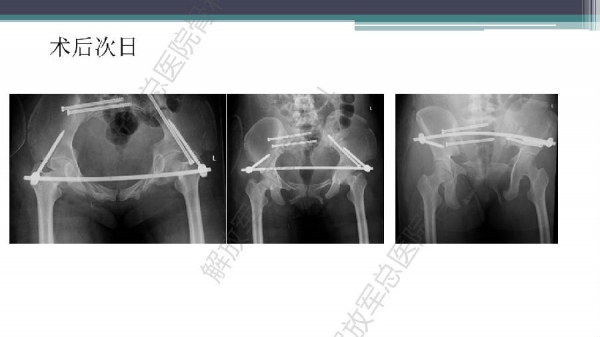

随着建筑和交通运输业的快速发展,合并骨盆、髋臼骨折多发伤、复合伤患者逐年增加,病死率和致残率都非常高。由于多发伤及复合伤、休克等往往不能在急性期对骨盆骨折进行确切复位及内固定,导致陈旧性骨盆骨折畸形愈合,从而产生一系列严重并发症,并且畸形矫正手术难度大、风险高、效果差。因此在抢救复苏后能不能尽早地、小切口甚至不切开、精确复位与固定骨盆骨折,防止陈旧性骨盆畸形愈合形成,成为广大骨科医生的挑战。解放军总医院创伤骨科在骨盆、髋臼骨折微创治疗方面做了一些工作,从微创理论探讨、到手术方法的改进,乃至钢板螺钉、微创复位器械等相继研发,形成了一系列的解决方案和配套内固定产品,为骨盆髋臼骨折的微创治疗奠定了基础。本幻灯则通过一例陈旧骨盆骨折畸形愈合的复杂治疗做引,通过介绍骨盆空间移位方式、透视特点、骨盆随意外架复位系统、复位原理以及1例典型病例的具体实施方案来综合、全面介绍我院微创骨盆髋臼骨折复位、固定新技术。